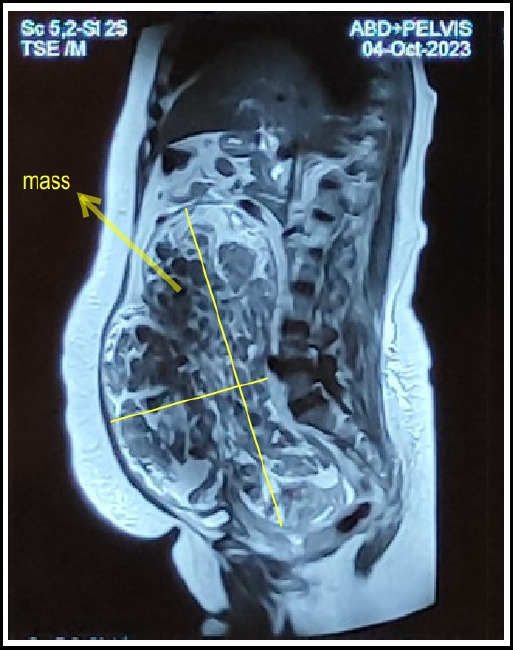

平滑肌瘤是一种常见的妇科疾病,影响20-30%的35岁以上妇女,绝经后患病率下降。平滑肌瘤最常见于子宫内。罕见的子宫外部位包括阔韧带、宫颈和阴道。我们报告一例罕见的多发性左阔韧带平滑肌瘤,从左髂窝和下胃延伸到上腹部。我们的病例强调了子宫外平滑肌瘤作为鉴别诊断的重要性,当患者出现巨大的腹部肿块怀疑是附件肿瘤或恶性肿瘤时。

Leiomyomas are a common gynaecological condition affecting 20-30% of women over the age of 35, with prevalence decreasing following menopause. Leiomyomas are most commonly found within the uterus. Rarer extra-uterine locations include the broad ligament, cervix, and vagina. We present an unusual case of multiple Left Broad Ligament Leiomyomata that extended from Left Iliac Fossa and Hypogastrium to Epigastric region in a 50-year-old female. Our case highlights the importance for extra-uterine leiomyoma to be considered as a differential diagnosis in patients presenting with huge abdominal mass suspicious of adnexal tumor or malignancy.